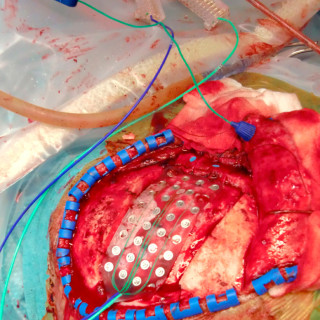

I USA er forekomsten av hjerneslag hos mennesker over 65 år gått ned de siste tiårene. I en studie som omfattet over 14 000 personer i fire byer i USA, ble det i perioden 1987 – 2011 registrert litt over 1 000 nye tilfeller av hjerneslag, hvorav nesten 90 % var iskemiske (1). Aldersjusterte insidensrater for en tiårsperiode var 0,69 (95 % KI 0,59 – 0,81) i aldersgruppen over 65 år og 0,97 (95 % KI 0,76 – 1,25) for dem under 65 år. Samlet gikk dødeligheten etter hjerneslag ned for hver tiårsperiode med en hasardratio på 0,80 (95 % KI 0,66 – 0,91). – Denne kohortstudien fra USA viser at...